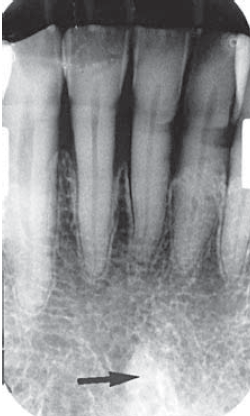

17. What is showing by arrow?

18. What is showing by arrow?

19. What is showing by arrow?

20. What is showing by arrow?